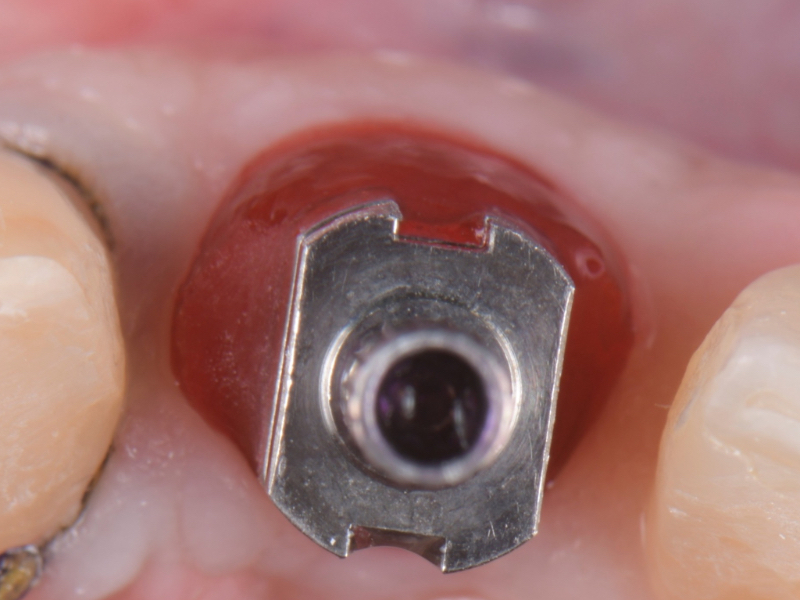

Once the optimal emergence profile has been developed, we need to communicate and transfer this information properly to the laboratory. Unfortunately, all implant companies provide stock round impression copings that do not precisely transfer the soft-tissue contours. A simple protocol to communicate this information is described here.

This visual essay walks through a step-by-step description of how to fabricate a personalized impression coping with transfer ofthe peri-implant tissue anatomy properly.

A step-by-step technique for fabricating a personalized impression coping was described to optimize the transfer of the peri-implant soft tissue architecture to the laboratory.